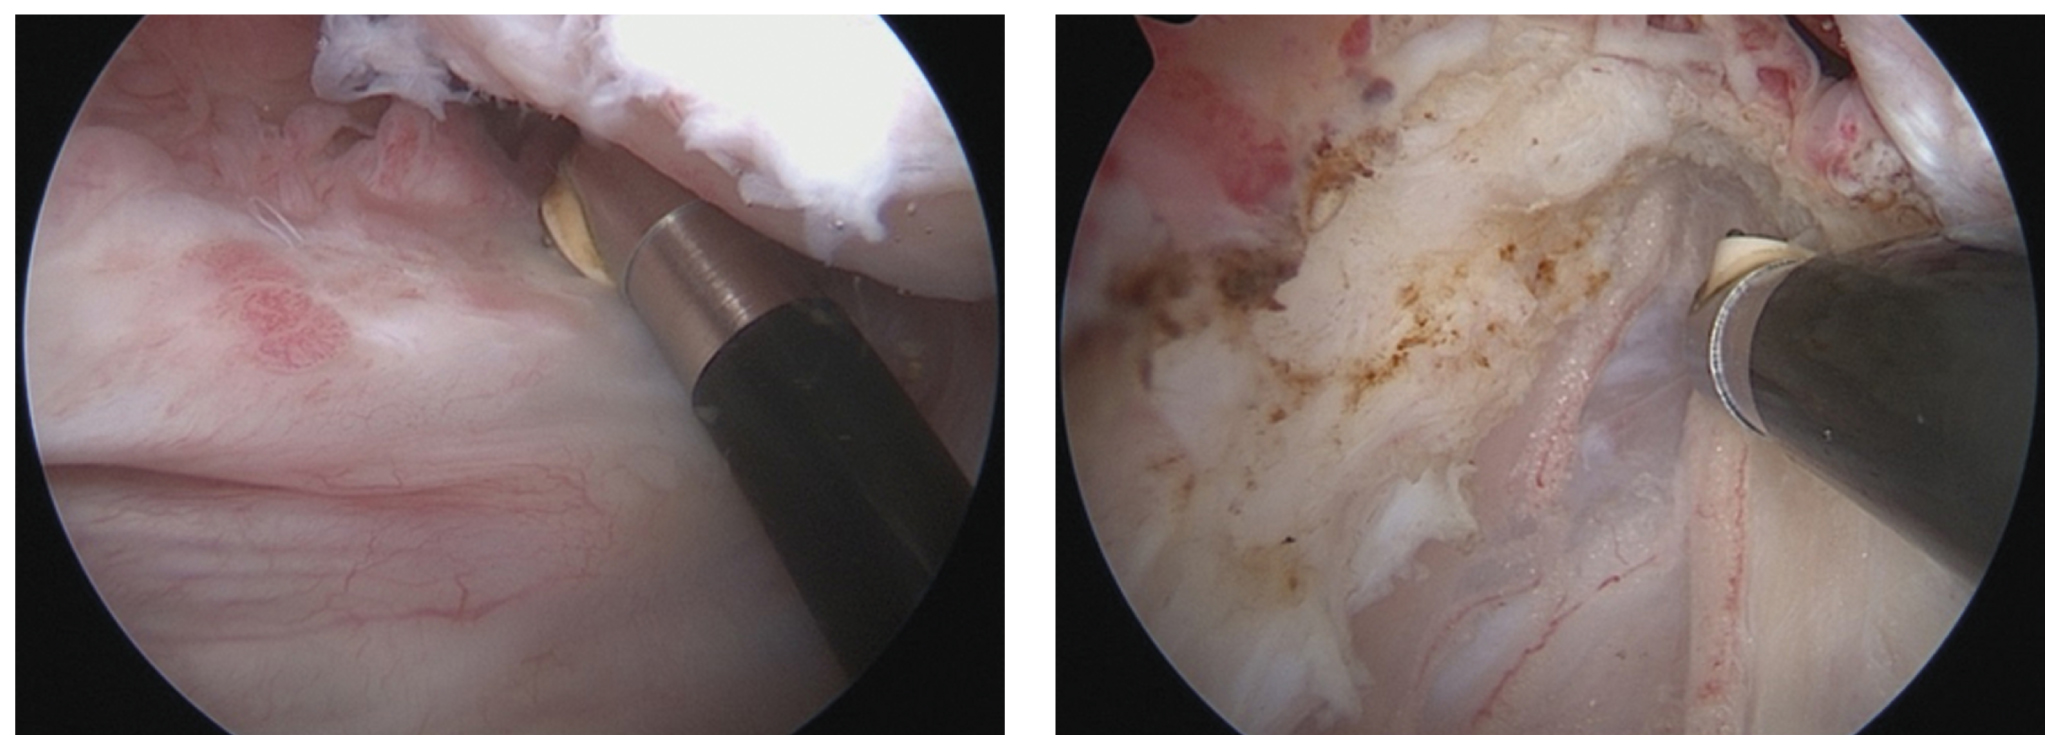

Техника комбинированного эндоскопического вмешательства подразумевает одномоментный ортопедический (артроскопия плечевого сустава) и нейрохирургический (эндоскопический невролиз) компонент. Операцию выполняли в положении пациента «пляжное кресло» под общей анестезией (эндотрахеальный наркоз). Использовали стандартную 30° оптику и стандартное оборудование для артроскопии крупных суставов. Доступ в полость сустава начинали с установки стандартного заднего порта в области «мягкой точки» [13]. Производили диагностическую артроскопию плечевого сустава с оценкой внутрисуставных структур (рис. 1).

Рис. 1. Эндоскопическая картина плечевого сустава: 1 — суставной отросток лопатки; 2 — головка плечевой кости; 3 — дегенеративно-измененная задняя фиброзно-хрящевая губа. / Fig. 1. Endoscopic view of the shoulder joint: 1 — glenoid; 2 — humeral head; 3 — degenerated posterior labrum.

После диагностического этапа артроскопии осуществляли лечебный этап по поводу внутрисуставной патологии, который включал тенотомию при явлениях теносиновита и повреждениях сухожилия длинной головки двуглавой мышцы плеча (рис. 2), восстановление вращательной манжеты плеча при ее повреждении, дебридмент при дегенеративных изменениях фиброзно-хрящевой губы, дебридмент и абразивную хондропластику шейвером и аблятором при наличии хондромаляции головки плечевой кости и/или суставного отростка лопатки.

Рис. 2. Выполнение тенотомии сухожилия длинной головки бицепса. / Fig. 2. Performing the tenotomy of the long head of a biceps.